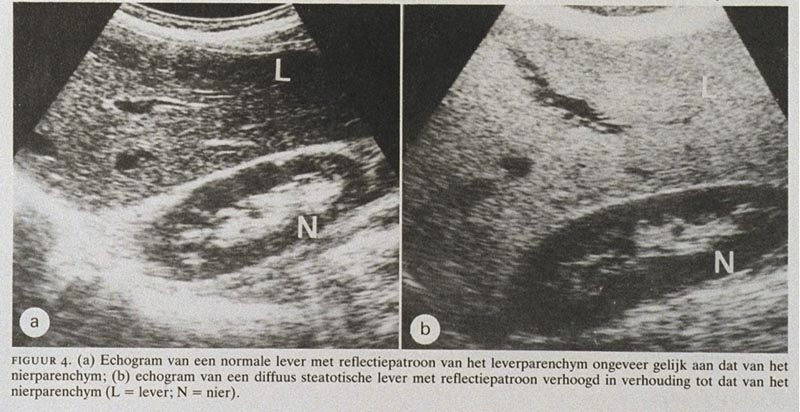

Dit is ter hoogte van de lever rechts boven op de buik tussen de 8e en de 9e rib. 024 361 65 04. If in a steatotic liver one or more focal relatively echo-poor lesions are detected on ultrasonography CT and or biopsy should be considered for definitive diagnosi.

De buikorganen zijn onder meer de lever milt pancreas galblaas nieren blaas enz. Tijdens een echografie worden met behulp van geluidsgolven organen onderzocht. If in a steatotic liver one or more focal relatively echo-poor lesions are detected on ultrasonography CT and or biopsy should be considered for definitive diagnosis author van Rooij W.